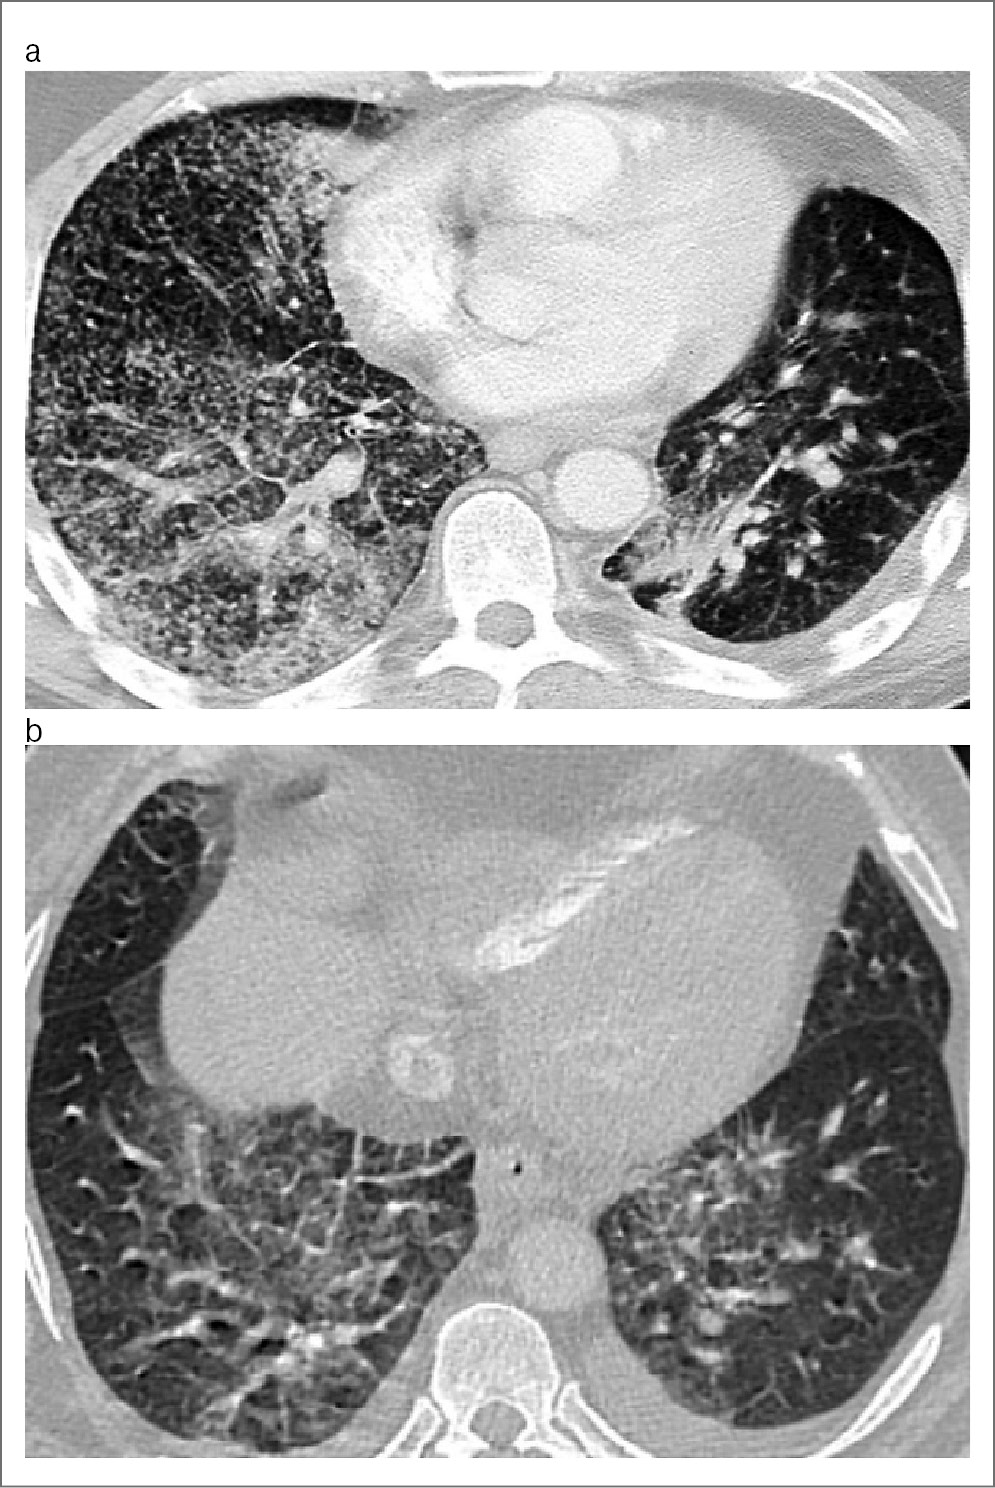

В качестве примеров приводим снимки КТ органов грудной клетки у больных IVВ стадией ВИЧ-инфекции с ИД в фазе прогрессирования и при отсутствии АРВТ, иллюстрирующие сходство визуализации патологических изменений в 1а и 1б группах (рис. 1, a, b) и в 2а и 2б группах (рис. 2, a, b).

Рис. 2. КТ органов грудной клетки. Аксиальная проекция, режим легочного окна: a – пациент, возраст 26 лет, с IVB стадией ВИЧ-инфекции с ИД в фазе прогрессирования, без АРВТ и с верифицированной коморбидностью ТОД, ЦМВП и КВП; b – пациент, возраст 28 лет, с IVB стадией ВИЧ-инфекции с ИД в фазе прогрессирования, без АРВТ и с верифицированной коморбидностью ТОД и ЦМВП.

Как видно на рис. 1 и 2, на снимках КТ органов грудной клетки визуализируются однотипные 4 синдрома: диссеминации, патологии плевры усиления и деформации легочного рисунка с участками «матового стекла» и аденопатии.